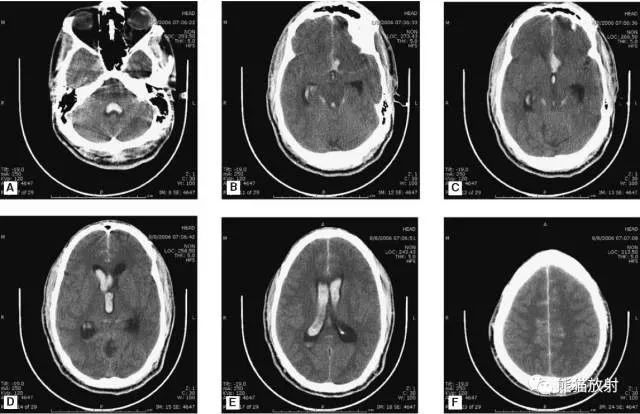

5、高血压性脑出血

高血压性脑出血:自发性出血;

继发于长期高血压及慢性血管病;

常见于基底节区、丘脑、脑桥、小脑。

A:占位效应,相邻脑沟、脑池消失;

F:脑出血破入四脑室。

▲钩回疝:

是当代偿机制不能适应占位性病变时的结果。

基底节区大量高血压性脑出血,破入脑室及蛛网膜下腔,周围水肿,脑干周围空间消失;脑干出血、脑积水。